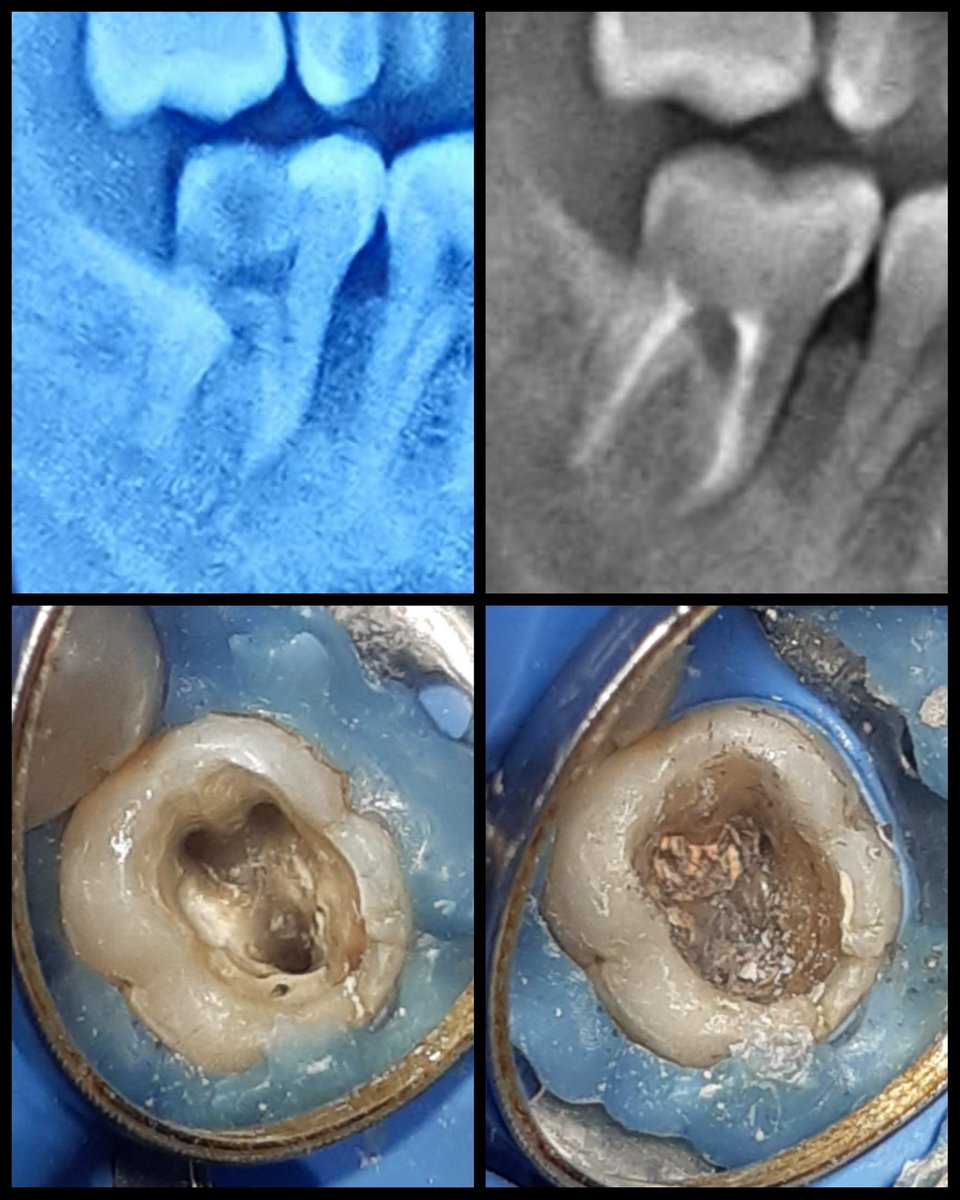

Gue jadi penasaran 🤣🤣🤣 it looks like our molars but lebih gede. Kalo mau PSA itu pake bor tembok kli ya buat open accessnya.. Hmmm..